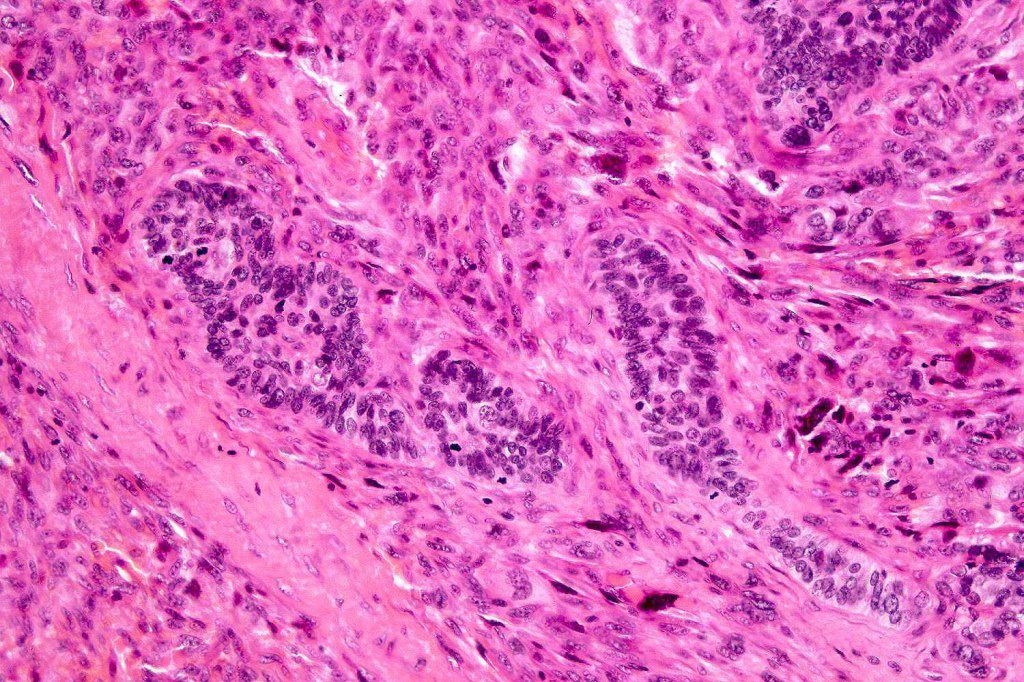

Carcinosarcoma

Cutaneous carcinosarcoma (metaplastic carcinoma, carcinoma with heterologous differentiation)

Histological features

•Osteoid

•Chondroid

•Smooth muscle

•MFH-like features with osteoclasts

•Neural differentiation